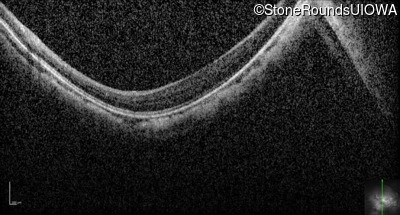

Optical Coherence Tomography - Right - 20/63 -1

Exemplar / OCT Stack